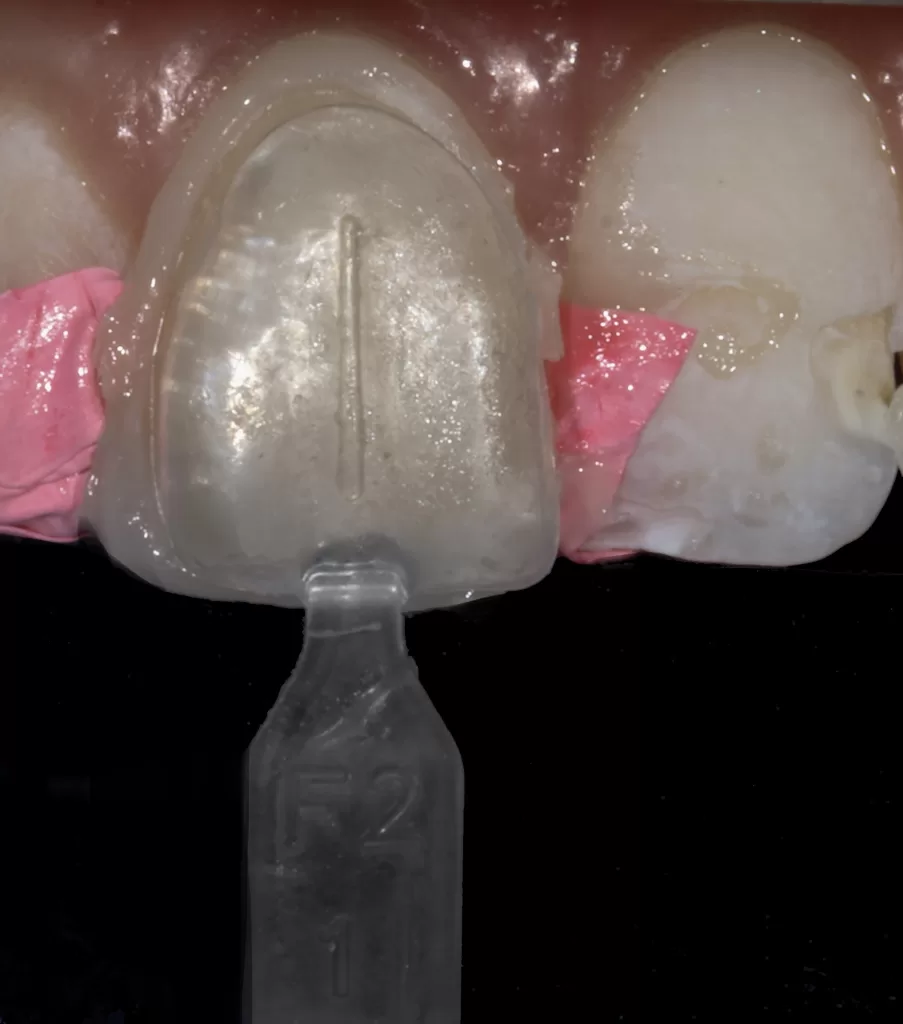

Figures 7a-7c: Uveneer right central labial build-up with packable composite.

- While uncured Uveneer Extra template with G-aenial Injectable Bleach White (GC, Bunkyo-ku, Tokyo, Japan) is pressed as the final layer (aligning the vertical groove on the Uveneer with the long axis of the tooth) and light cured (Figs 7a-7c). Repeat steps 6-11 for the adjacent veneered teeth (Fig 8a).

Once the palatal aspect has been established using the Paladex, the facial is built using a first layer of packable composite that is light cured followed by a second packable composite layer pressed with the Uveneer and left uncured. The Uveneer is then lined with high filler flowable composite (Figs 7a-7c, 8a-8c & 14), pressed onto the uncured second layer of packable composite and cured together; reproducing the aesthetically natural facial anatomy based on Dr. Jan Hajtó’s natural ‘Anteriores’.13